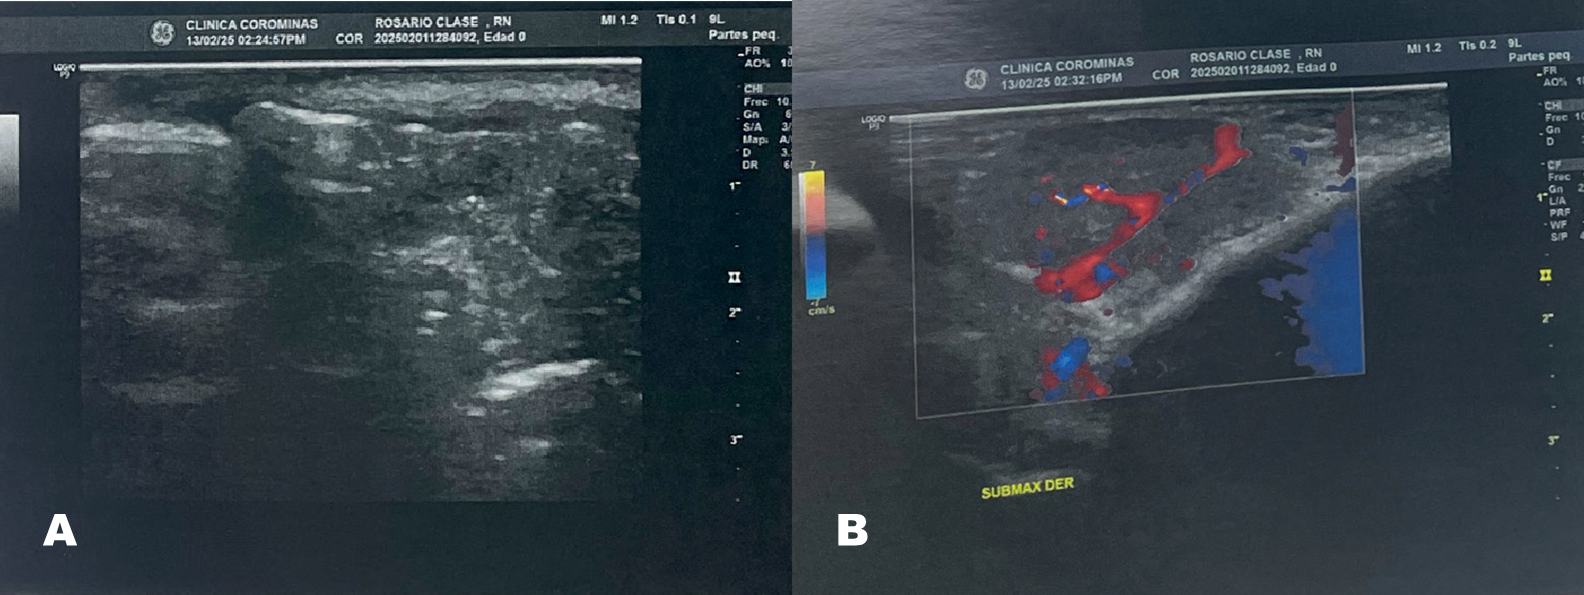

Figura 2. Ultrasonido de partes blandas a nivel de submaxilar derecho

Fuente: expediente clínico.

La Figura 2 muestra imagen heterogénea con centro vascularizado que mide 2.7 x 1.7 cm. Impresión diagnóstica de adenopatía submaxilar derecha.